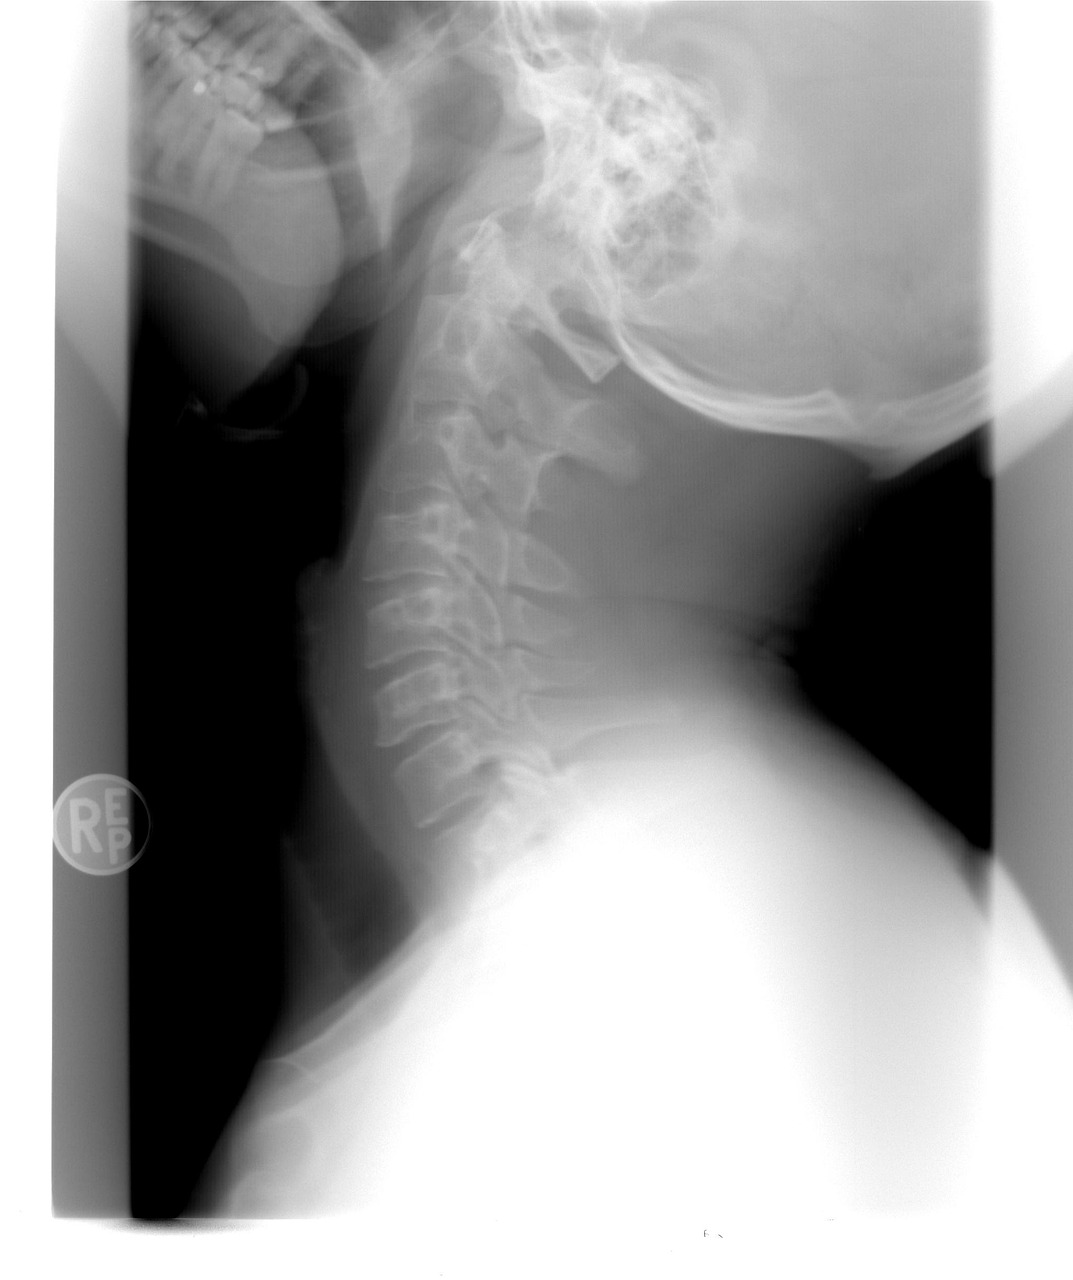

경추손상이 의심되는 경우, 정확한 진단을 위해 X-레이, CT, MRI 등의 영상진단 방법이 사용됩니다.

이를 통해 척추의 손상 여부, 척수나 신경의 손상 정도를 파악할 수 있습니다.